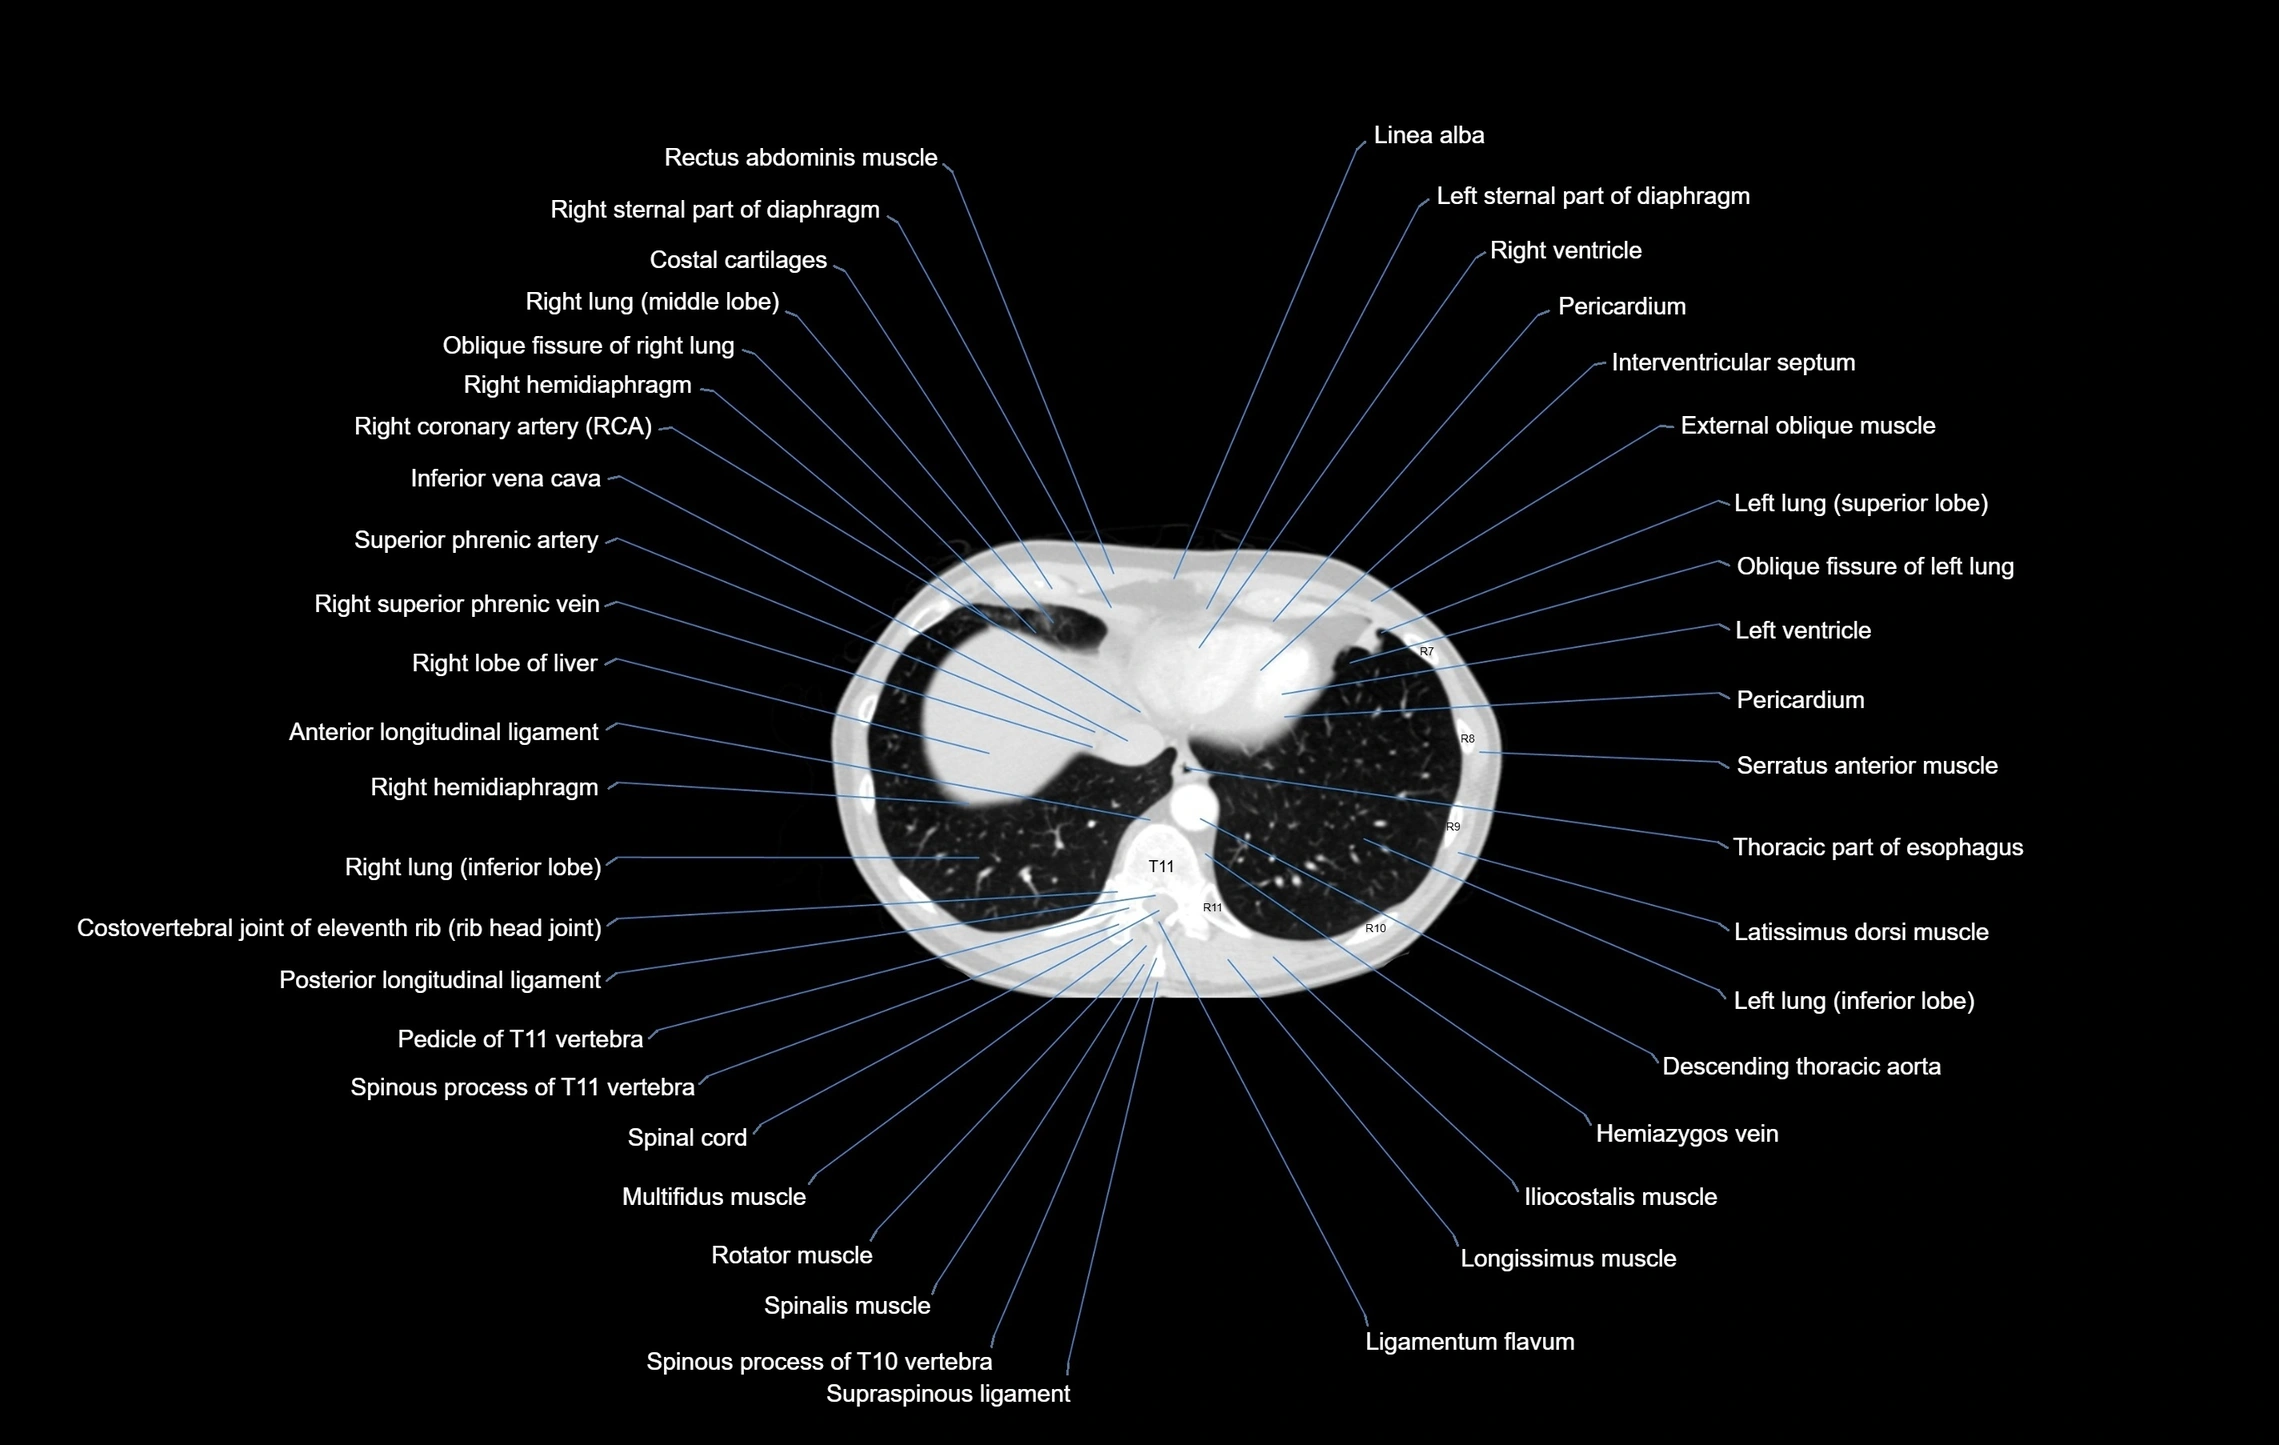

- Rectus abdominis muscle

- Sternal part of diaphragm

- Costal cartilages

- Right lung (middle lobe)

- Oblique fissure of right lung

- Right hemidiaphragm

- Right coronary artery (RCA)

- Inferior vena cava

- Superior phrenic artery

- Right lobe of liver

- Right ventricle

- Pericardium

- Interventricular Septum

- External oblique muscle

- Left Lung (Superior Lobe)

- Oblique fissure of left lung

- Left ventricle

- Serratus anterior muscle

- Thoracic part of esophagus

- Latissimus dorsi muscle

- Left lung (inferior lobe)

- Descending thoracic aorta

- Hemiazygos vein